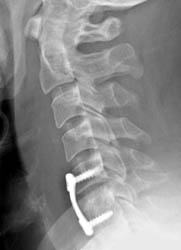

Lateral radiograph taken 1 day after surgery. The cortical screws

and the anterior plate appear well seated. There is prevertebral soft tissue

swelling, consistent with the recent surgery. |